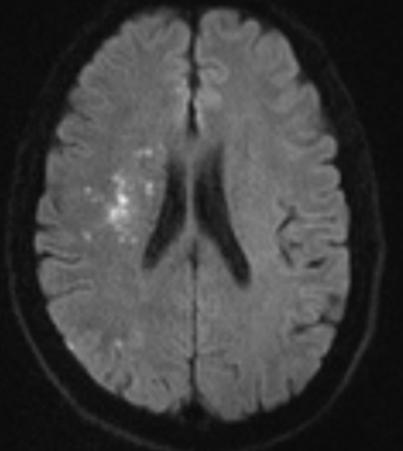

辅助检查:头颅MRI+MRA提示急性多发梗塞灶,右侧颈内动脉未见显影。

MRA示右侧颈内动脉未见显影

右侧大脑半球、基底节区多发梗塞灶

(急性期)